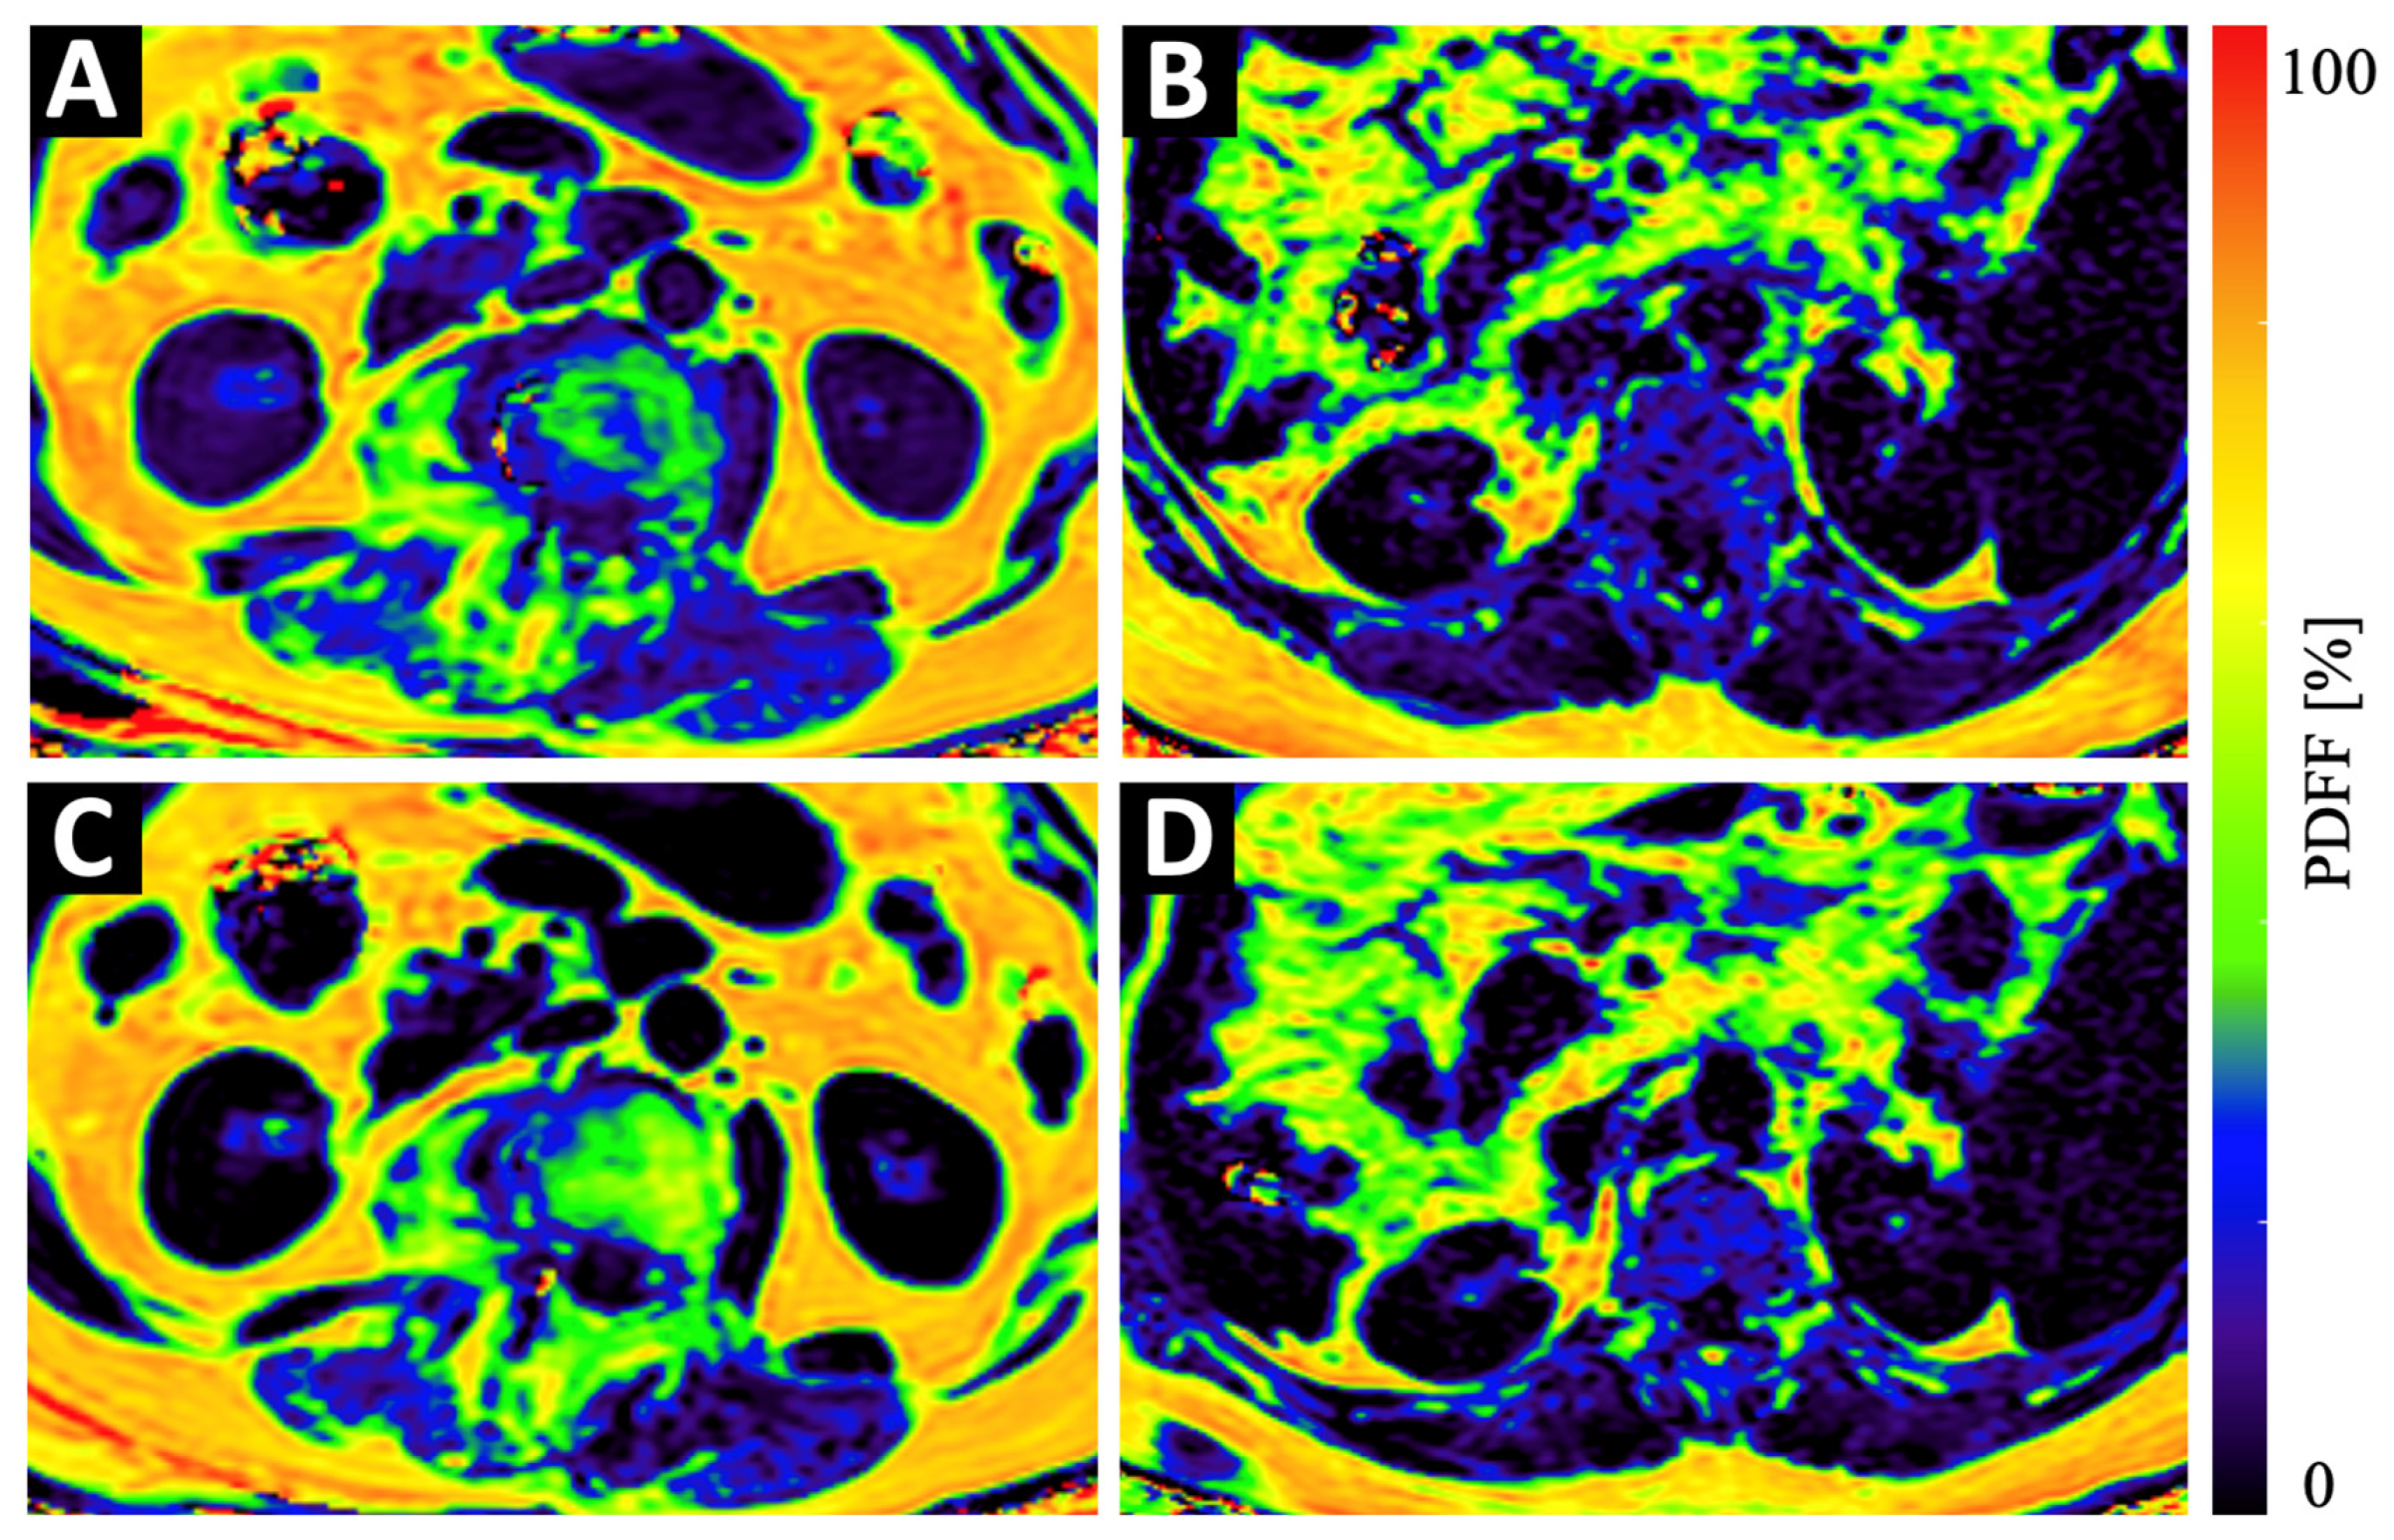

Figure 3.

Example color-coded PDFF maps of a 84-year old osteopenic (BMD = 107 mg/cm3) female patient (A,C) and a 69-year old male patient with normal BMD values (123 mg/cm3) (B,D) at baseline (A,B) and 6 months follow-up (C,D). Although the maps of the osteopenic patient (A,C) show a strong increase in PDFF in vertebral bone and in the PSM, the increase in the maps of the non-osteopenic/osteoporotic patient (B,D) show only a very subtle increase in PDFF.